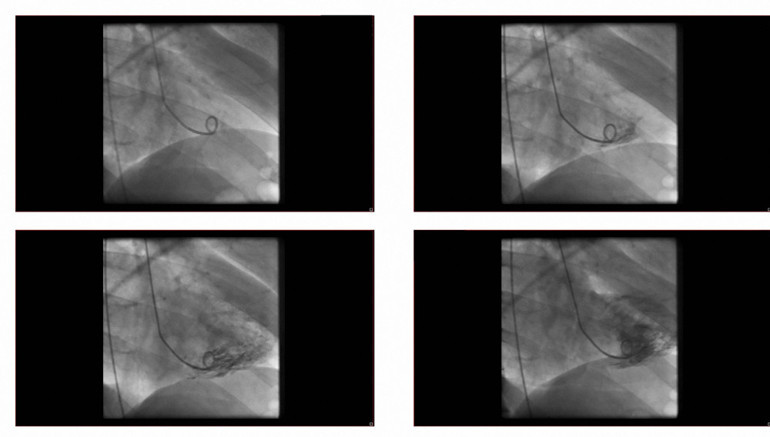

Bilgisayarlı tomografi (BT) / Anjiyografi:

Kullanılan kontrast maddeler iyot (iodine) içerir. Bu maddeler X-ışınlarını güçlü şekilde soğurur.Böylece kontrast verilen bölgeler görüntüde daha parlak görünür.